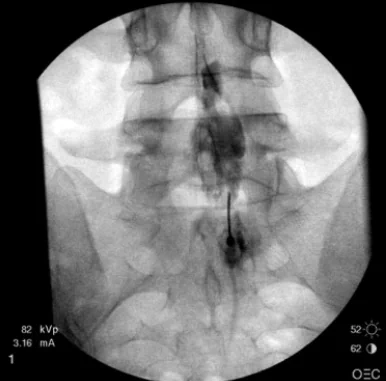

- Epidural block – Low backache with radiculopathy, postherpetic neuralgia, Phantom limb, cancer pain

- Coeliac Plexus block – Chronic pancreatitis, Hepatocellular carcinoma